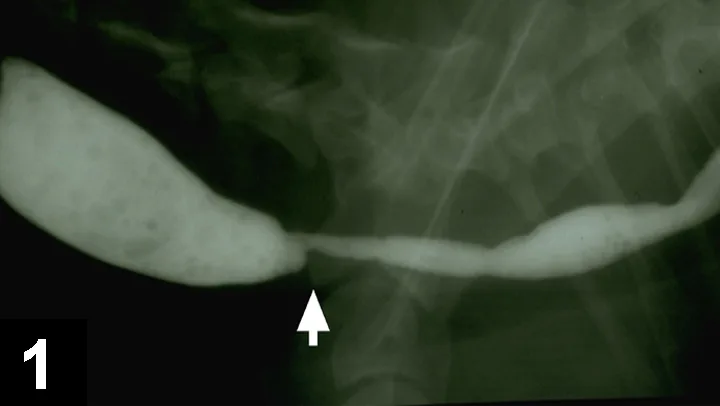

Radiographs. Thoracic and abdominal radiographs are considered normal. A liquid barium contrast study is performed, and no obvious abnormalities are detected. Because the regurgitation episodes are worse when associated with ingestion of solid food and less with liquids, a barium-food esophagram should be performed. Figure 1 is a barium-food esophagram that shows a narrowing of the esophagus at the thoracic inlet with esophageal dilatation cranial to the defect. Endoscopy might be performed rather than the barium-food esophagram if it is available in the practice.

Figure 1. A barium-food mixture esophagram showing dilatation of the cervical esophagus with a luminal narrowing at the thoracic inlet (arrow)